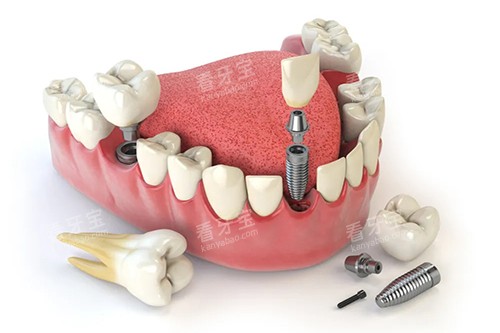

其中,小切口黑科技是张月鹏口腔的一大特色。

这种技术在种植牙、牙齿矫正等领域具有明显的优势。

小切口技术可以减少手术创伤,缩短患者的修养时间,降低患者的痛苦。